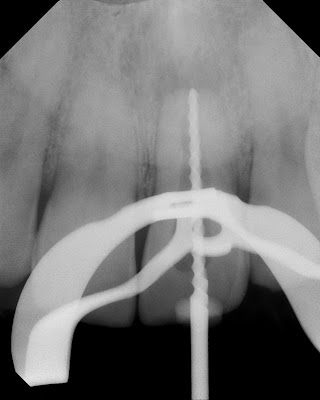

Retreatment elected. The old, poorly condensed gutta percha was removed.

Because of the open apex, MTA was selected as the obturation material. Coronal barrier placed to allow for internal bleaching.

After course of antibiotics and bleaching treatment, the tooth is asymptomatic, less mobile and fully functional again.